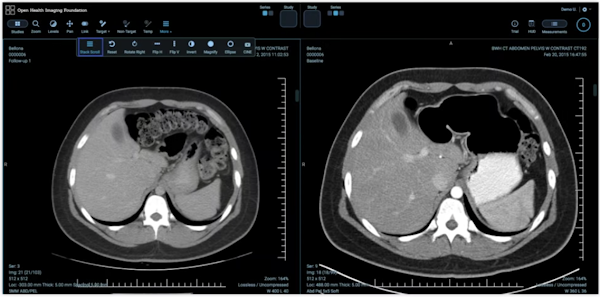

Penyimpanan gambar

Cloud Healthcare API memungkinkan pertukaran data yang mudah dan aman menggunakan standar DICOMweb internasional untuk pencitraan. Cloud Healthcare API menyediakan lingkungan pengembangan tingkat perusahaan yang sangat skalabel dan terkelola sepenuhnya, serta menyertakan kemampuan bernilai tambah, seperti de-identifikasi DICOM otomatis. Partner teknologi pencitraan mencakup NetApp untuk pengelolaan data lokal yang lancar ke cloud, dan Change Healthcare, sebuah perusahaan berbasis cloud yang membuat PACS dengan pencitraan aplikasi untuk penggunaan klinis oleh ahli radiologi.